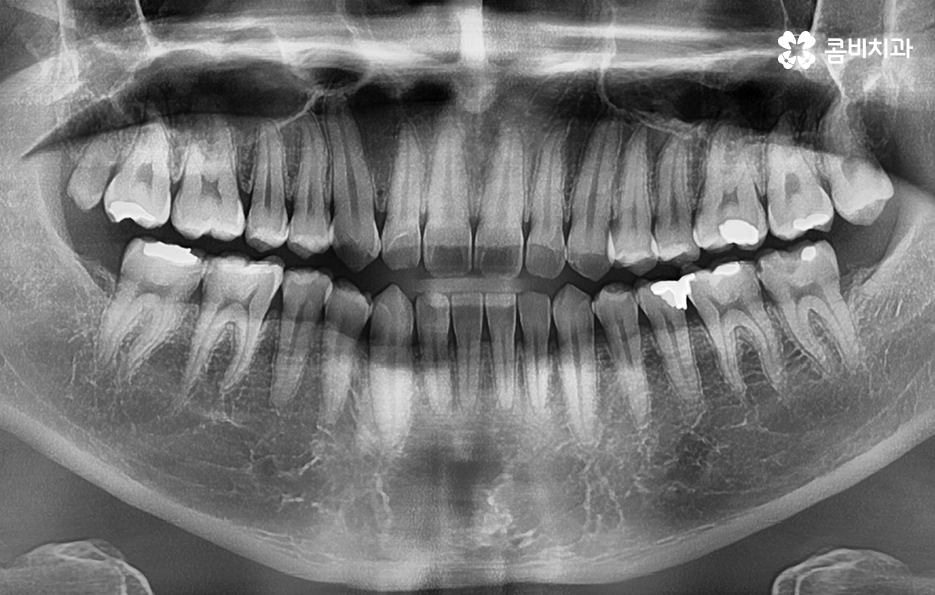

치아 중에서도 어금니는 저작력에 있어서 압력을 상당히 많이 받는 부위이기 때문에 어금니가 한번 깨지는 경우에 큰 치료로 이어지는 경우가 많으며 초기에 치아 끝 부분이 살짝 깨지는 문제와는 달리 어금니 충치 깨짐 처럼 이미 약해졌던 치아가 한번 크게 깨질 경우에는 신경치료나 발치로도 이어지는 경우가 많기 때문에 나이가 들수록 빈번하게 발생되는 어금니 파절에 대해 잘 이해하시고 대처하시길 바라고 있어요

일반적으로 어금니가 깨질 때 유독 딱딱한 음식을 씹다가 깨진다거나 하는 특정 상황이 계기가 되는 경우가 많기 때문에 환자분들의 입장에서는 운이 좋지 않았다고 생각하기 쉽지만 어금니 깨짐의 요인은 정말 운이 안좋았던 상황 보다 오히려 기존에 치아가 서서히 마모되고 손상되다가 발생되거나 충치가 발단이 되는 경우가 더 많기 때문에 평소 치아 관리에 대해 전체적으로 점검할 필요가 있는데요

나이가 들수록 오래된 보철물이 탈락되거나 깨지면서 치아의 손상이 함께 발생되는 사례가 정말 많은데 이러한 문제는 보통 언제 치료를 받았던건지 기억도 안나던 오래된 보철물에서 문제가 발생되는 사례가 많이 있어요

재료마다 차이는 있지만 보철물의 일반적인 수명은 약 10년 정도로 예상하며 각 환자분들에 따라서 식습관이나 생활습관 등의 차이가 있기 때문에 보다 빨리 수명이 다하는 경우도 있고 더 오래 쓰는 경우도 있겠지만 10년 정도면 아무리 단단한 보철물도 접착제가 녹아서 틈이 발생되기 쉬우며 그로 인해 세균이 틈 사이로 침투하여 2차 충치가 발생되는 경우가 많이 있어요

특히 위 환자분의 사례처럼 아말감의 경우에는 빠르고 저렴한 치료 자체는 장점이 있지만 아말감의 특성상 주변 치아가 변색될 우려부터 치아와의 접착이 좀더 빠르게 약해질 우려가 있는 보철물이며 아말감이 조금씩 깨지면서 틈 사이로 충치가 발생되는 사례도 많기 때문에 어금니 충치 깨짐의 경우 보편적으로 보철물 내부에 2차 충치가 발생되면서 치아 내부의 충치가 드러나는 경우가 많고 충치가 없던 경우에는 기존의 치아에 지속적인 마모와 손상이 거듭되다가 치아의 내구성이 약해져서 결국 깨지면서 문제가 드러나는 경우가 많을 거예요